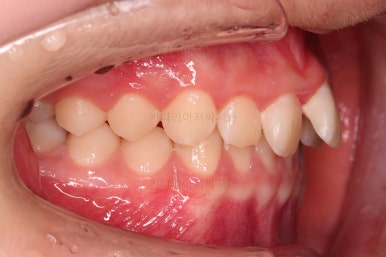

1. 초진

초진 시 입안의 모습입니다.

눈에 띄는 부분은 당연히 앞니가 삐뚤고, 앞니 하나가 앞으로 튀어나온 모습인데요.

자세히 관찰해 보면 다른 문제점들이 보입니다.

우선 위아래 앞니가 깊숙히 맞물려 있는 과개교합 양상인데요.

✅ 앵글씨 2급 부정교합

이번 환자분은 앵글씨 2급 부정교합이었는데요.

정상교합에 비해서 윗니가 상대적으로 앞에 아랫니가 상대적으로 뒤에 위치한 부정교합이 앵글씨 2급 부정교합입니다.

이번 환자분은 어금니가 위아래가 지그재그 서로 엇갈려 꽉 끼이는 교합이 아니라 1대1로 치아가 부딪혀 있는 상태였습니다.